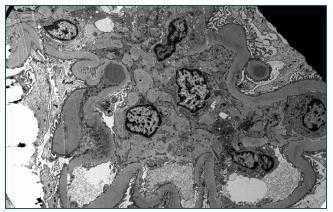

Dada la rápida progresión de la IR, sin haber podido aclarar la etiología, se indica la realización de una biopsia renal en la que se objetivan 21 glomérulos, seis esclerosados y los restantes con expansión mesangial glomerular, apreciándose en uno de ellos una semiluna. Engrosamiento de la membrana basal tubular e infiltrado inflamatorio intersticial moderado, con predominio de células plasmáticas, polimorfonucleares neutrófilos y linfocitos. El estudio de inmunofluorescencia es negativo. Con microscopia electrónica se demuestra engrosamiento difuso de la membrana basal glomerular, con la presencia de depósitos electrón-densos subepiteliales que configuran los típicos humps (figura 1).

Con estos hallazgos se llega al diagnóstico de glomerulonefritis de origen postinfecciosa (GNPI) complicando una nefropatía diabética (ND).

Figura 1. M.E: GN Postinfecciosa. Presencia de depósitos electrón-densos subepiteliales (humps).